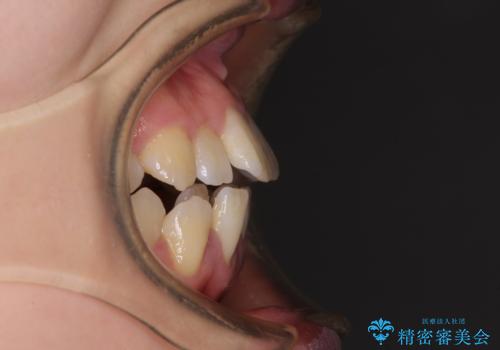

- 上下前歯の隙間と口元の出っ張った感じを気にして来院された患者様です。

上下の隙間は舌突出癖によるもので、またその癖により前歯が前方に出ている状態でした。

口元の出っ張りを改善するため、上下左右第一小臼歯4本を抜去し、ワイヤー装置にて矯正治療を行うこととしました。